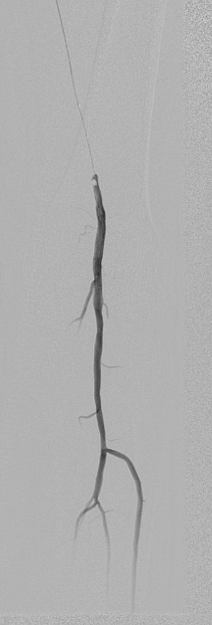

图为:术中造影评估 髂股段

图为:术中造影评估 膝下踝下段